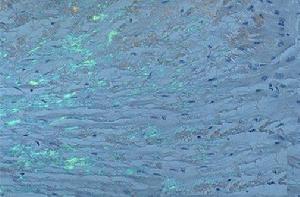

系統性澱粉樣變性病理圖1.澱粉樣輕鏈蛋白(AL) AL蛋白由部分或整個免疫球蛋白輕鏈組成,也可能為兩者的混合體輕鏈片段可能為N-末端或整個可變區。在AL中γ鏈比K鏈更多見AL蛋白見於原發性及骨髓瘤相關型澱粉樣變。

澱粉樣物質形成的確切機制尚未完全弄清,但澱粉樣原纖維沉積的先決條件,是其前體蛋白產生的量過多或有結構異常前體蛋白經不完全降解後成為易於摺疊成反向平行的β-片層結構片段而在家族性澱粉樣變多發性神經病及血液透析相關型澱粉樣變時,完整的未經降解的TTR及β2-M分子,也可形成澱粉樣原纖維。蛋白質的一級結構對其能否形成澱粉樣原纖維非常重要,如在遺傳性澱粉樣變時,單個胺基酸置換就可使原來不能形成澱粉樣物質的野生型分子變成能產生原纖維的突變型分子。此外,還有一些其他因素對原纖維的沉積過程及分布等有影響統稱之為澱粉樣促進因子(amyloid enhancing factor,AEF)可能與臨床上的個體差異有關。澱粉樣蛋白形成的機制。